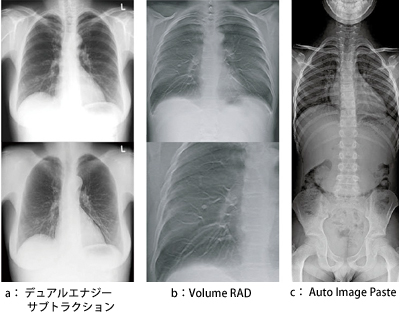

GEは今回,最新の一般撮影フラグシップモデル「Discovery XR656」で初めてFlashPadを搭載,“デュアルエナジーサブトラクション”(図2 a),“Volume RAD”(トモシンセシス,図2 b),“Auto Image Paste”(長尺撮影,図2 c)の3つのアドバンスドアプリケーションに対応できる性能を持たせた。基本性能として,200μmピクセル,CsI間接変換方式,1枚成型という特長を備え,1照射の線量が少ない場合でも,低ノイズ画像データが取得できるよう,“低線量&高DQE”のコンセプトも兼ね備えている。また,マルチフレームイメージング技術を採用し,すべてのアプリケーションで200μmピクセルビニングなしのままで,2022×2022×14ビットのピクセルデータを読み取り可能にし,臨床での応用範囲を拡大することに成功した。

図2 アドバンスドアプリケーション